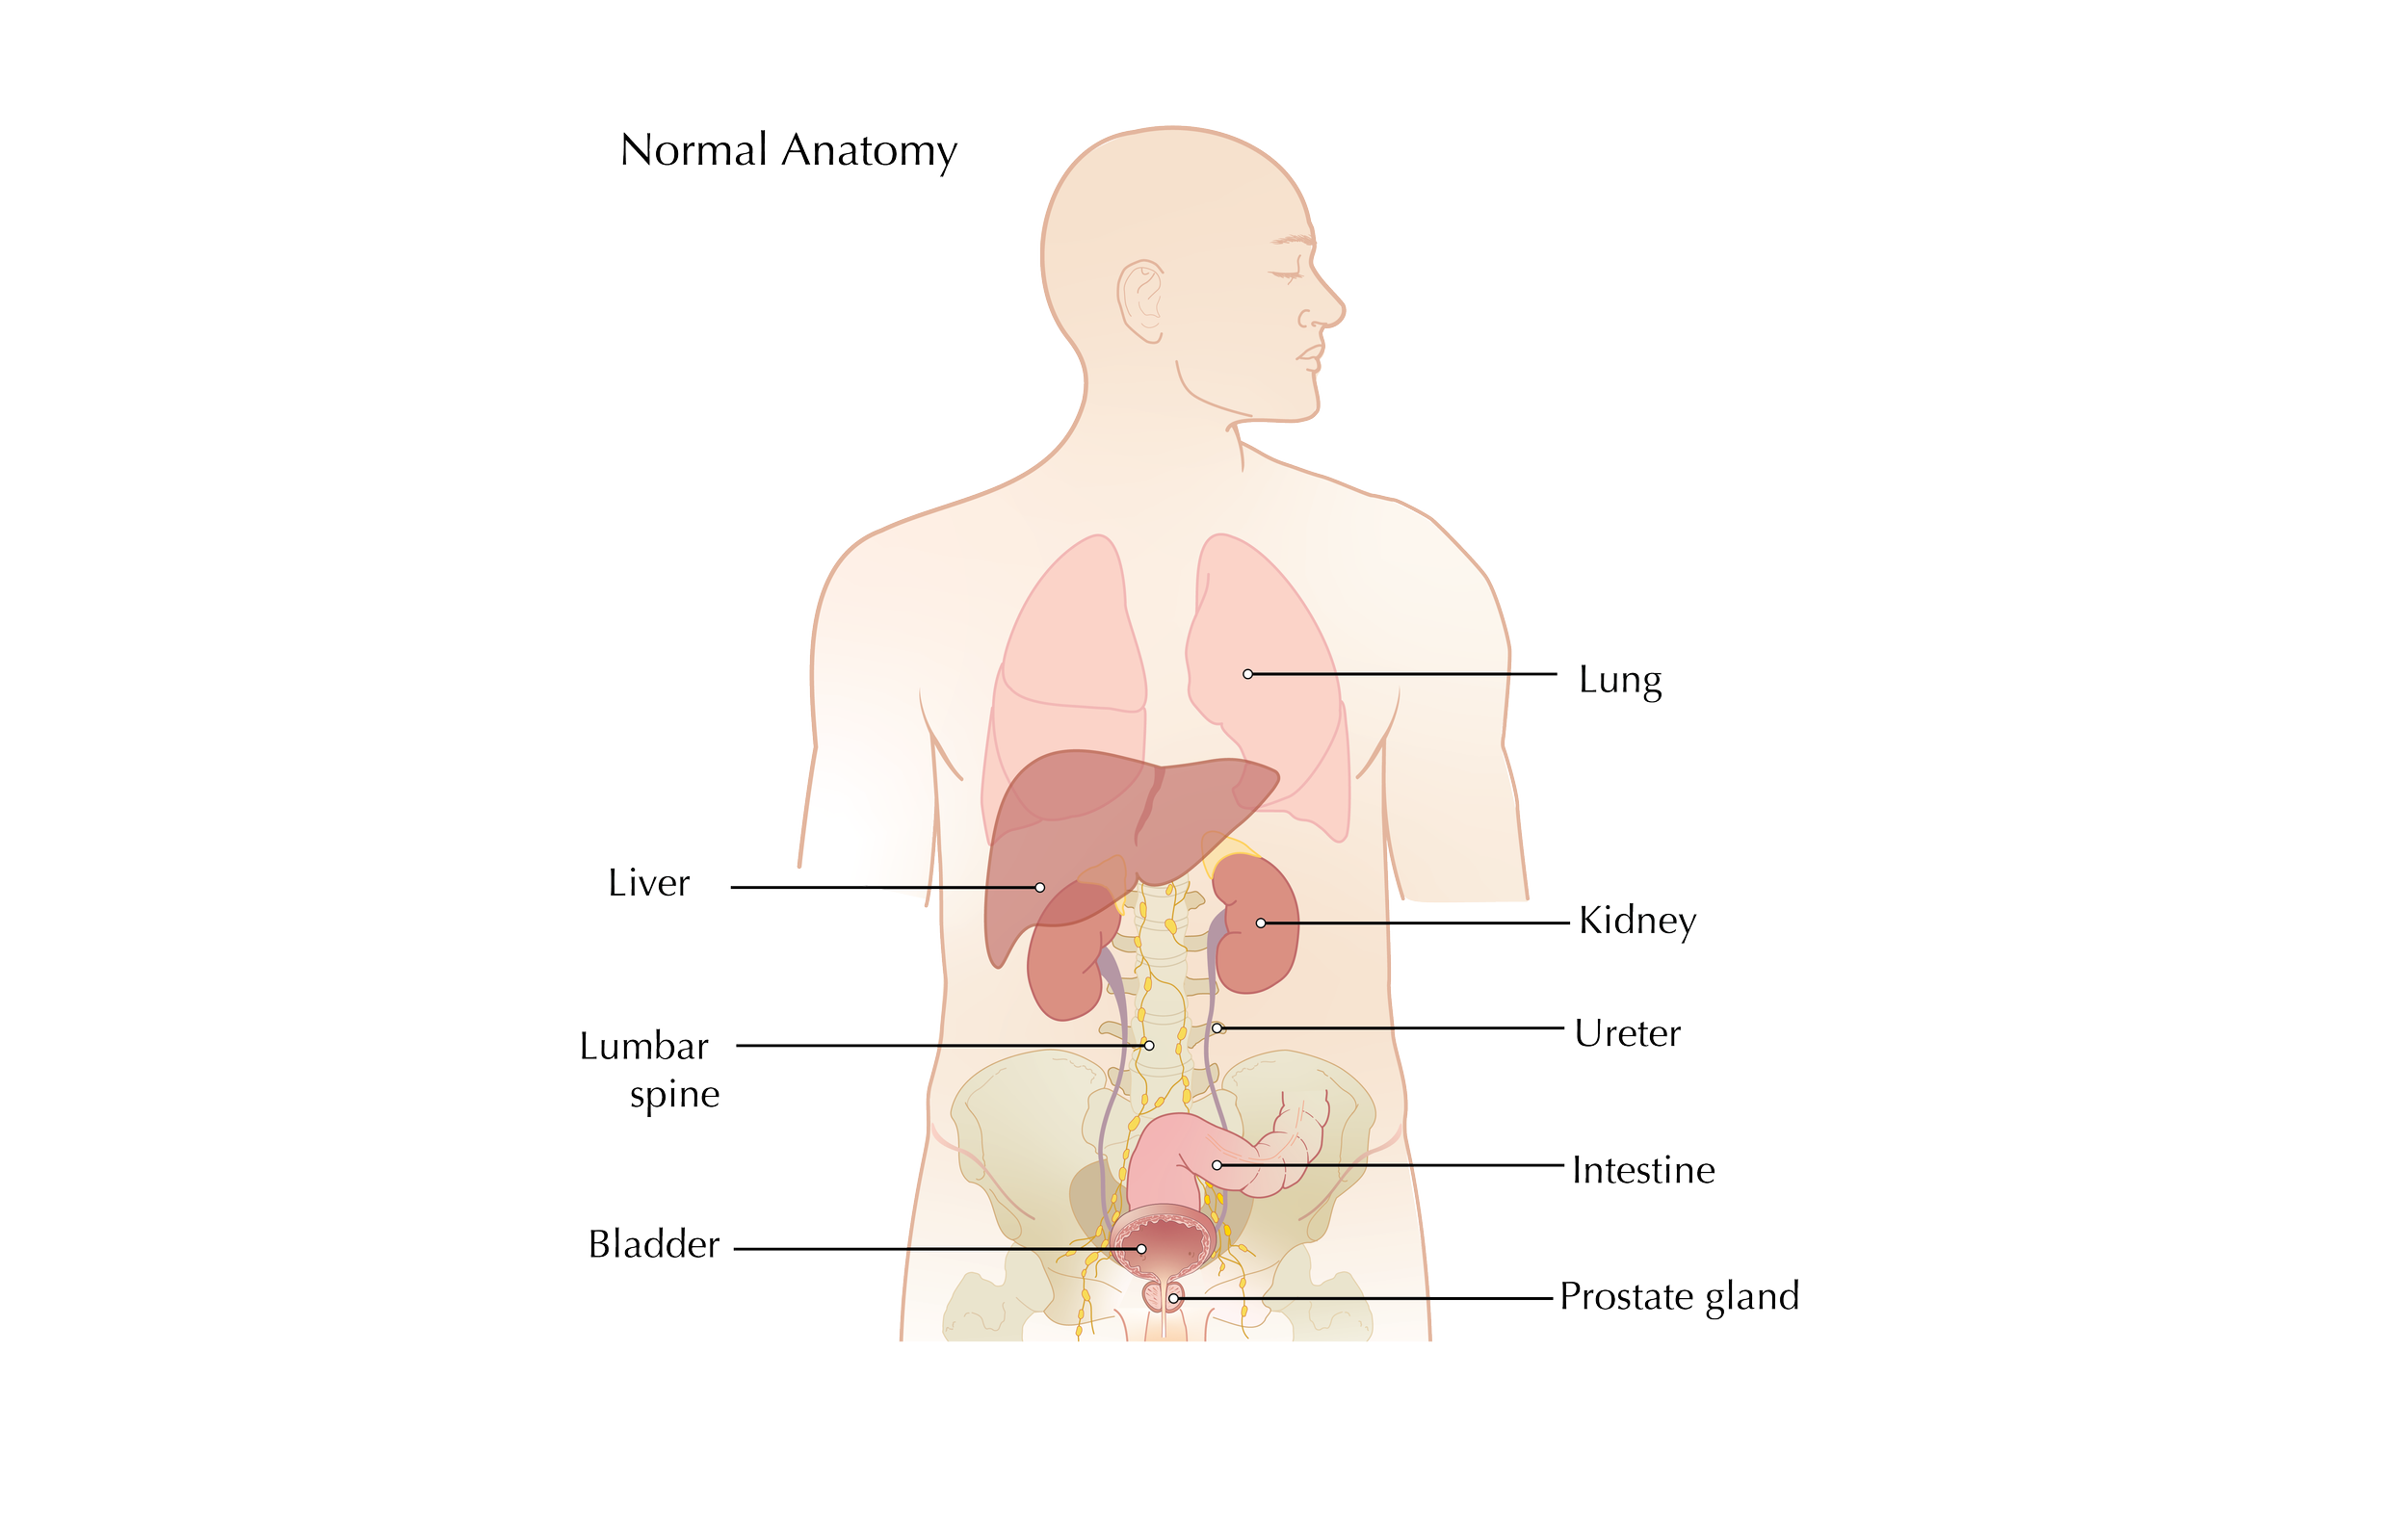

Prostate Cancer Booklet

Created clear, accurate, and visually engaging medical illustrations for a patient education booklet on prostate cancer for a hospital system. The illustrations simplified complex anatomical and clinical concepts, helping patients better understand diagnosis, treatment options, and disease progression.

Client: Northwell Hospital System

Patient Education: Prostate Cancer